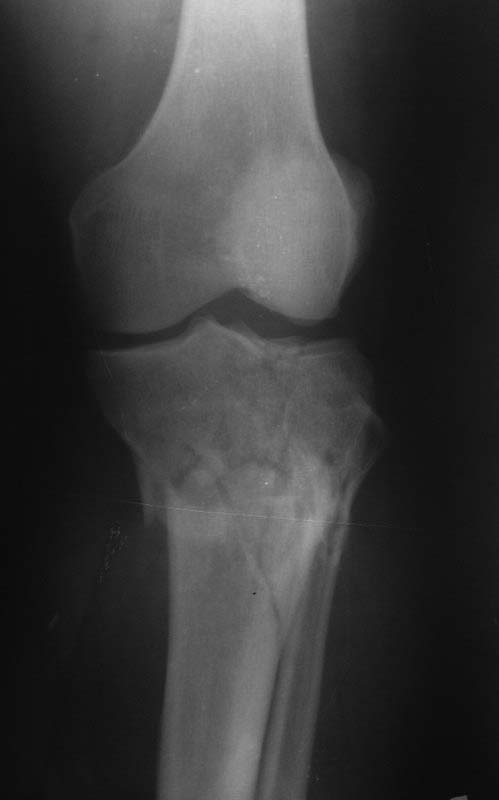

Внутрисуставной перелом в/3 б/берцовой кости |

Уважаемые коллеги.Прошу помочь с тактикой оперативного лечения данного перелома. Пациент 52 лет. Травма получена 22.12.13.ДТП. Находится на скелетном вытяжении. Планируем дистракциюв аппарате (база на мыщелки бедренной кости и база на голень). После чего малоинвазивно пластину. Вопрос: как лучше и менее травматично устранить смещение? Лучше ли без аппарата,открыто? Коллеги,уверен у вас большой опыт лечения подобных переломов. Буду очень признателен если поделитесь. Заранее спасибо.